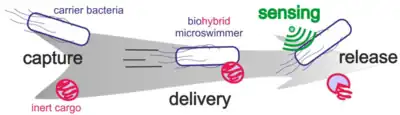

Biohybrid microswimmers

The so-called biohybrid microswimmer can be defined as a microswimmer that consist of both biological and artificial parts, for instance, one or several living microorganisms attached to one or various synthetic parts. The biohybrid approach directly employs living microorganisms to be a main component or modified base of a functional microswimmer.[150][151] Initially microorganisms were used as the motor units for artificial devices, but in recent years this role has been extended and modified toward other functionalities that take advantage of the biological capabilities of these organisms considering their means of interacting with other cells and living matter, specifically for applications inside the human body like drug delivery or fertilisation.[152][153][68]

A distinct advantage of microorganisms is that they naturally integrate motility and various biological functions in a conveniently miniaturised package, coupled with autonomous sensing and decision-making capabilities. They are able to adapt and thrive in complex in vivo environments and are capable of self-repair and self-assembly upon interaction with their surroundings. In that sense, self-sufficient microorganisms naturally function very similar to what we envision for artificially created microrobots: They harvest chemical energy from their surroundings to power molecular motor proteins that serve as actuators, they employ ion channels and microtubular networks to act as intracellular wiring, they rely on RNA or DNA as memory for control algorithms, and they feature an array of various membrane proteins to sense and evaluate their surroundings. All these abilities act together to allow microbes to thrive and pursue their goal and function. In principle, these abilities also qualify them as biological microrobots for novel operations like theranostics, the combination of diagnosis and therapy, if we are able to impose such functions artificially, for example, by functionalisation with therapeutics. Further, artificial extensions may be used as handles for external control and supervision mechanisms or to enhance the microbe's performance to guide and tailor its functions for specific applications.[68]

In fact, the biohybrid approach can be conceived in a dualistic way, with respect to the three basic ingredients of an in vivo microrobot, which are motility, control, and functionality. Figure 1 illustrates how these three ingredients can be either realized biologically, i.e., by the microorganism, or artificially, i.e., by the synthetic component. For example, a hybrid biomicromotor based on a sperm cell can be driven by the flagellum of the sperm or by an attached artificial helical flagellum.[154][155] It can orient itself autonomously via biological interactions with its surroundings and other cells, or be controlled and supervised externally via artificial sensors and actuators. Finally, it can carry out a biological function, like its inherent ability to fertilize an egg cell, or an artificially imposed function, like the delivery of synthetic drugs or DNA vectors. A biohybrid device may deploy any feasible combination of such biological and artificial components in order to carry out a specific application.[68]

Only a few decades later, microswimmers aiming to become true microscale surgeons evolved from an intriguing science-fiction concept to a reality explored in many research laboratories around the world, as already highlighted by Metin Sitti in 2009.[180][1] These active agents that can self-propel in a low Reynolds number environment might play a key role in the future of nanomedicine, as popularised in 2016 by Yuval Noah Harari in Homo Deus: A Brief History of Tomorrow.[181] In particular, they might become useful for the targeted delivery of genes [182] or drugs [183][184] and other cargo [185][186] to a certain target (e.g. a cancer cell) through our blood vessels, requiring them to find a good, or ideally optimal, path toward the target avoiding, e.g., obstacles and unfortunate flow field regions.[156]